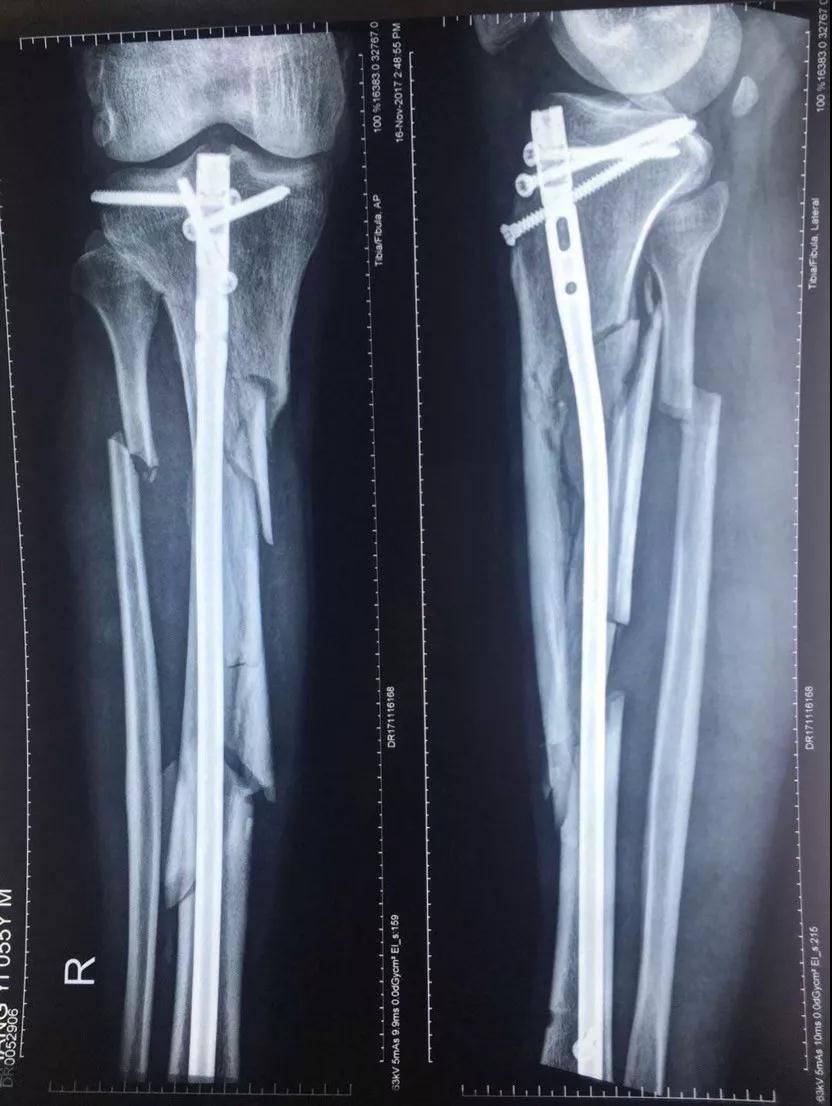

2017年10月18日十九大召開的當天下午五點多鐘,我像往常一樣去師範學院院裏老人居住的地方吃晚飯,此時,早已等待在老人樓下的一輛無牌照車裏出來四個蒙面人將我的腿打斷後逃走,這是十九大召開的的當日,是光天化日之下在大學的校園裏,是當着校園裏的教職工的面有預謀有組織的謀害。住院手術之後該團伙依然繼續到新院區繼續騷擾威脅,楊XX指使醫院會計在未履行任何財務手續的情況下從城南醫院挪用現金一千一百萬元,從兒媳婦XX也屬於城南醫院個人卡河北農信尾號XXXX中轉走五百萬元,此情況已經向安次區刑警隊和廊坊市公安局趙進晉局長報案’,至今至我傷殘和挪用醫院資金幕後指使依然逍遙法外。

2017年10月18日,張院長在廊坊師範學院院內遭受4名歹徒毆打至右腿粉碎性骨折,4名歹徒和背後指使者趙XX 均已落案。